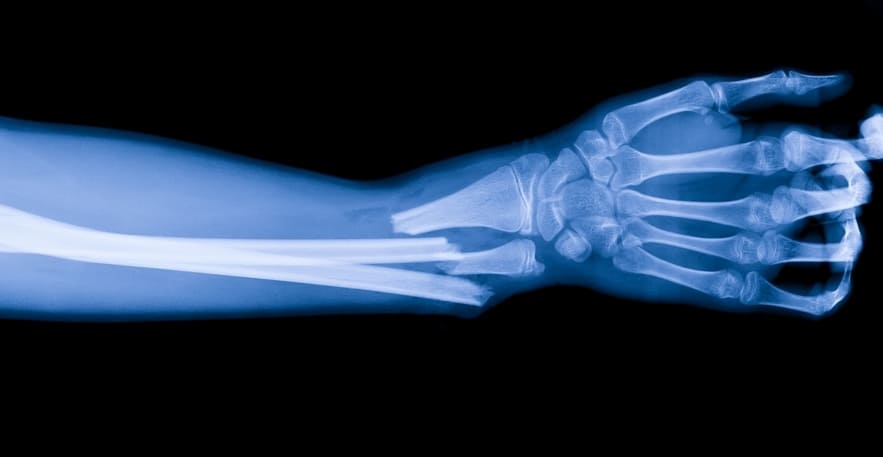

Является лучшим методом лечения переломов. При поражении костей кисти или дистальной части сустава лучевой кости применяется чрескостный остеосинтез спицами. Перелом костных структур предплечья устраняют с помощью внутрикостного остеосинтеза, накостного остеосинтеза лучевой кости пластинами.